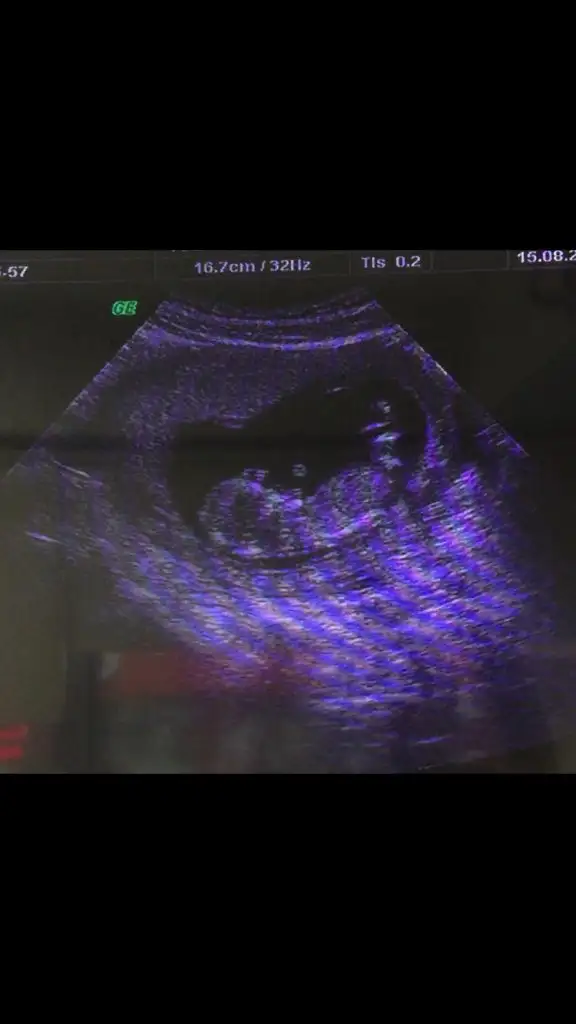

Biri kız biri erkeksordum ama daha erken dedibi de şimdi bunları ,çektim videodan belki yardımcı olur

Canım soldaki kız sağdaki erkek.foto da soldakinden emin olamamıştım videoda daha net.nub çizgisi göremiyorum.kafa yapılarına göre yorum yaptım.sonucu öğrenince yazarsınsordum ama daha erken dedibi de şimdi bunları ,çektim videodan belki yardımcı olur

teşekkürler canım.öğrenince yazacağımCanım soldaki kız sağdaki erkek.foto da soldakinden emin olamamıştım videoda daha net.nub çizgisi göremiyorum.kafa yapılarına göre yorum yaptım.sonucu öğrenince yazarsın

Sol erkek sağ kızsordum ama daha erken dedibi de şimdi bunları ,çektim videodan belki yardımcı olur